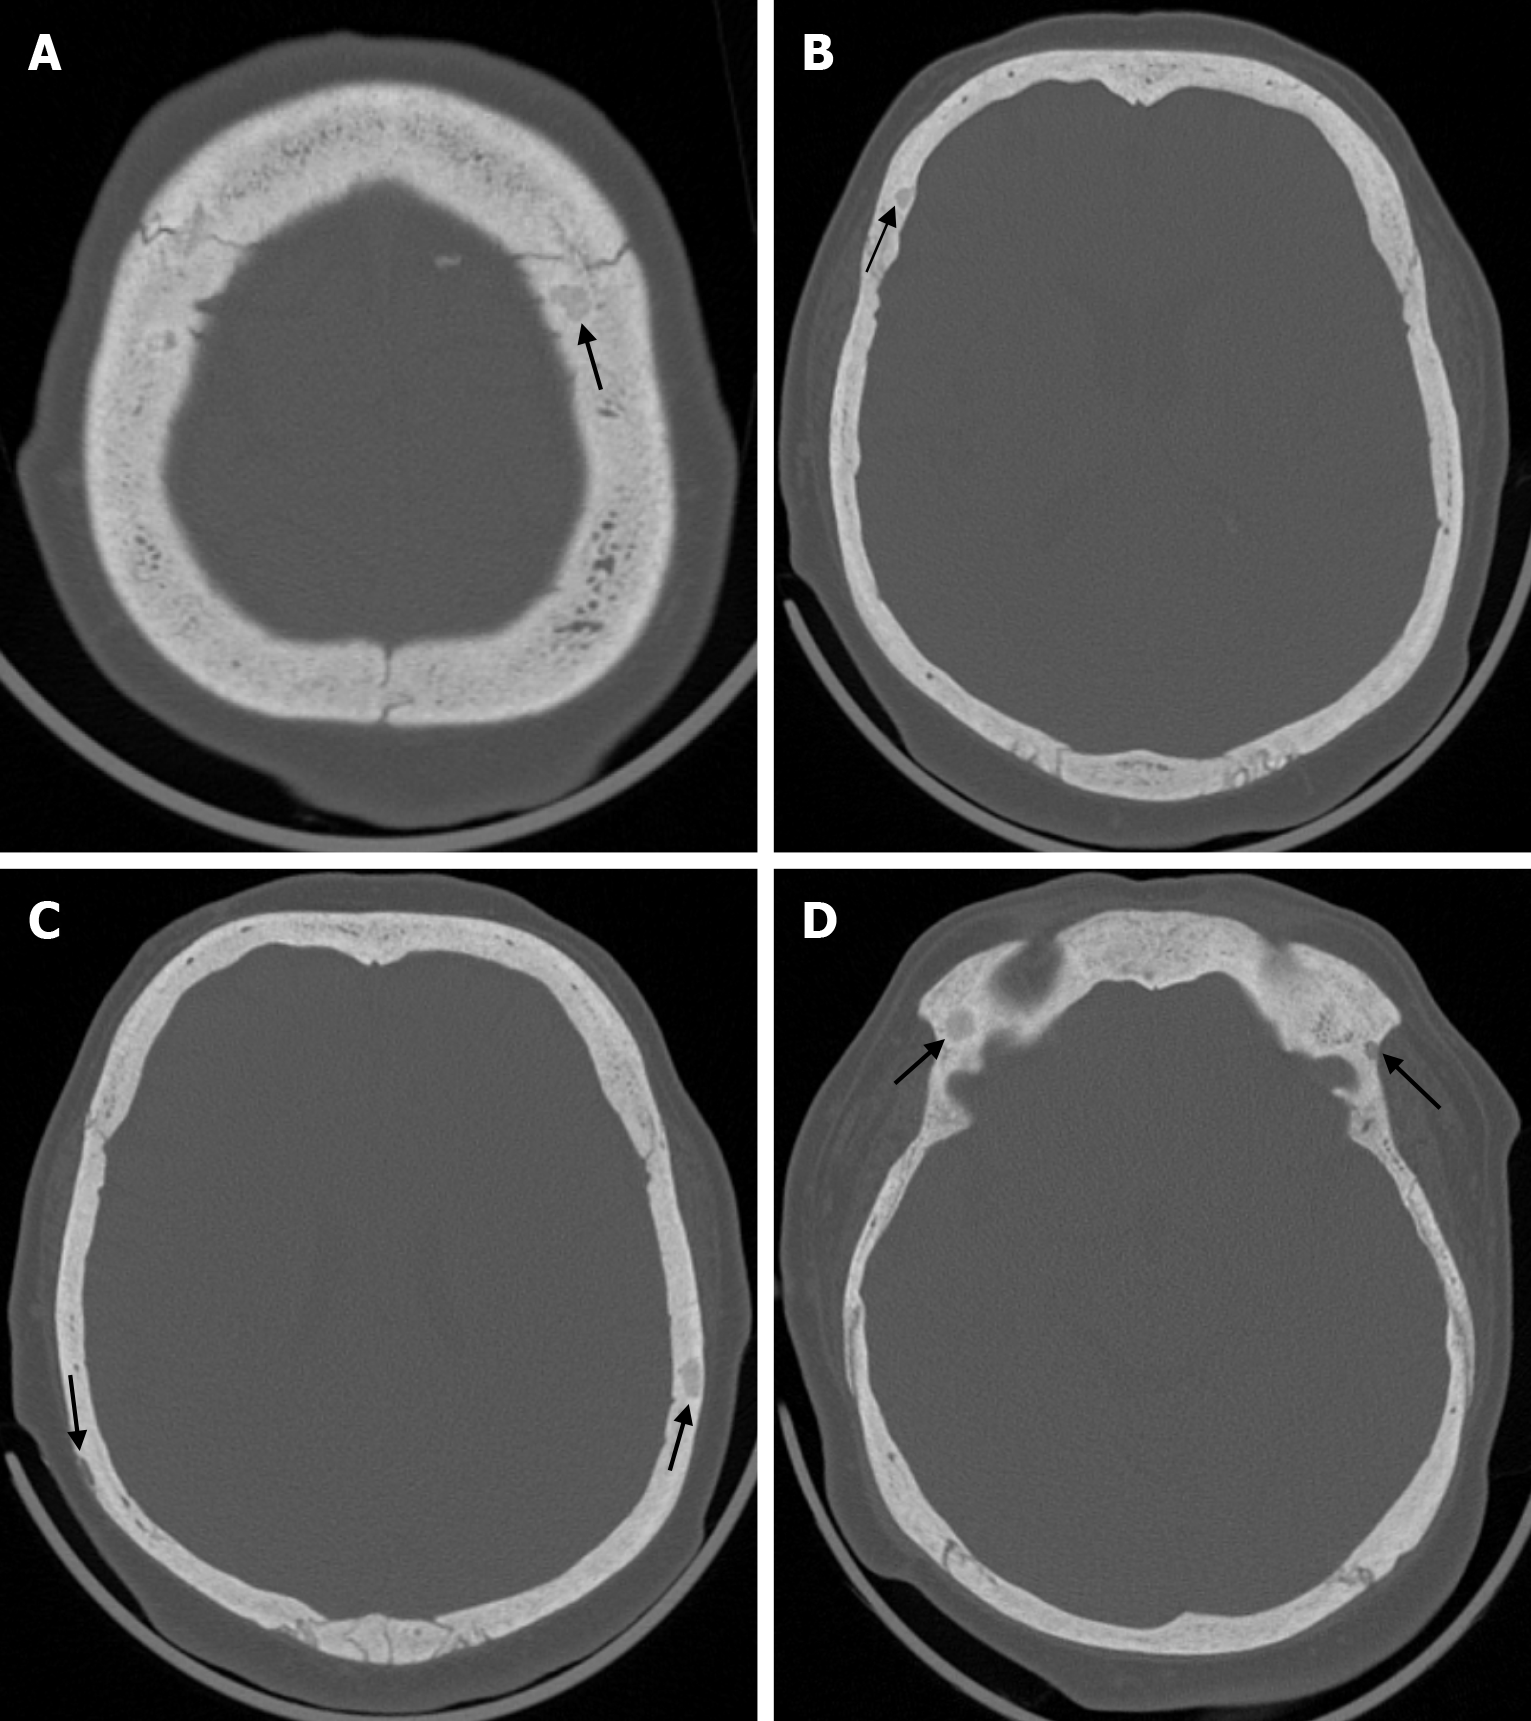

Skeletal changes in chronic anemia are due to ineffective erythropoiesis as a result of impaired haemoglobin synthesis, peripheral destruction of erythrocytes and consequently reduced erythrocyte lifespan. Radiography show massive hyperplasia of the bone marrow associated with hyperactivity of the bone marrow in response to anemia. The hair-on-end sign is seen on plain radiography of the skull, CT and MRI as long, thin vertical lines of calcified spicules perpendicular to the bone surface, appearing as upright hairs. The hair-on-end appearance of the skull is a characteristic feature of chronic haemolysis, usually seen in patients with thalassaemia (Figure 14) and sickle cell disease. The incidence of hair-on-end appearance in patients with thalassaemia is 8.3%. Although rare, the hair-on-end sign has also been described in iron deficiency anemia, sickle cell disease, cyanotic congenital heart disease, hematological malignancies and nutritional deficiencies. The appearance of these projections indicates excessive medullary erythropoiesis in patients and is rare before the age of 5 years. As the bone lesions are explained by the relationship between proliferating bone marrow and bone cortex, only hypertransfusion initiated early in life will prevent the development of the abnormality[55].

The prevalence of cranial osteomyelitis is 1.5% of all osteomyelitis cases, with a mortality rate of 20%-40%[45]. In developed countries, postoperative craniotomy infections are the most common cause of osteomyelitis, whereas in developing countries, sinusitis and scalp infections are the most common causes. It may occur as a complication of hematogenous spread or trauma. CT findings in the acute phase of osteomyelitis include areas of rarefaction and loss of diploic bone trabeculae; demineralization, erosion or thinning of the cortical bone table; and extracranial and subperiosteal abscesses. Diploic bone sclerosis and cortical bone thickening, radiolucent areas, and cortical disruption may occur in the chronic phase. Sequestration occurs as a result of the destruction of the skull base. On MRI may reveal an intracranial extension, particularly an epidural abscess and/or a subdural empyema. MRI findings in the acute phase of osteomyelitis include inflammatory replacement of diploic bone fat, widening of the diploic space, thinning of the skull base, increased signal intensity on T2-weighted images and contrast enhancement on T1-weighted images (Figure 12). In the chronic phase, sequestration, contrast enhancement in soft tissues and dura, and destruction of cortical bone fragments are seen. Bone scans using technetium-99m, gallium-67 citrate, single-photon emission computed tomography (SPECT), PET or PET-CT scans with 18F-fluorodeoxyglucose are highly effective in detecting cranial bone infections[46].